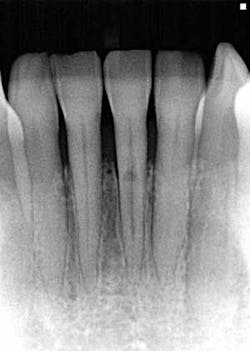

I offer the four clinical examples below to help you distinguish between internal and external resorption.- The outline of the canal in No. 24 is easily seen through the lesion, unaltered, and appearance is slightly ragged and irregular (figure 5).

- Diagnosis given to the patient at the time lesion was first noticed: internal resorption. As you can see, a root canal was completed, but no changes noted to the lesion. Patient continued to have discomfort post root canal therapy (figure 6).

- Reassessment: external resorption confirmed by a 3-D scan. Tooth was recommended for removal and an implant was placed.